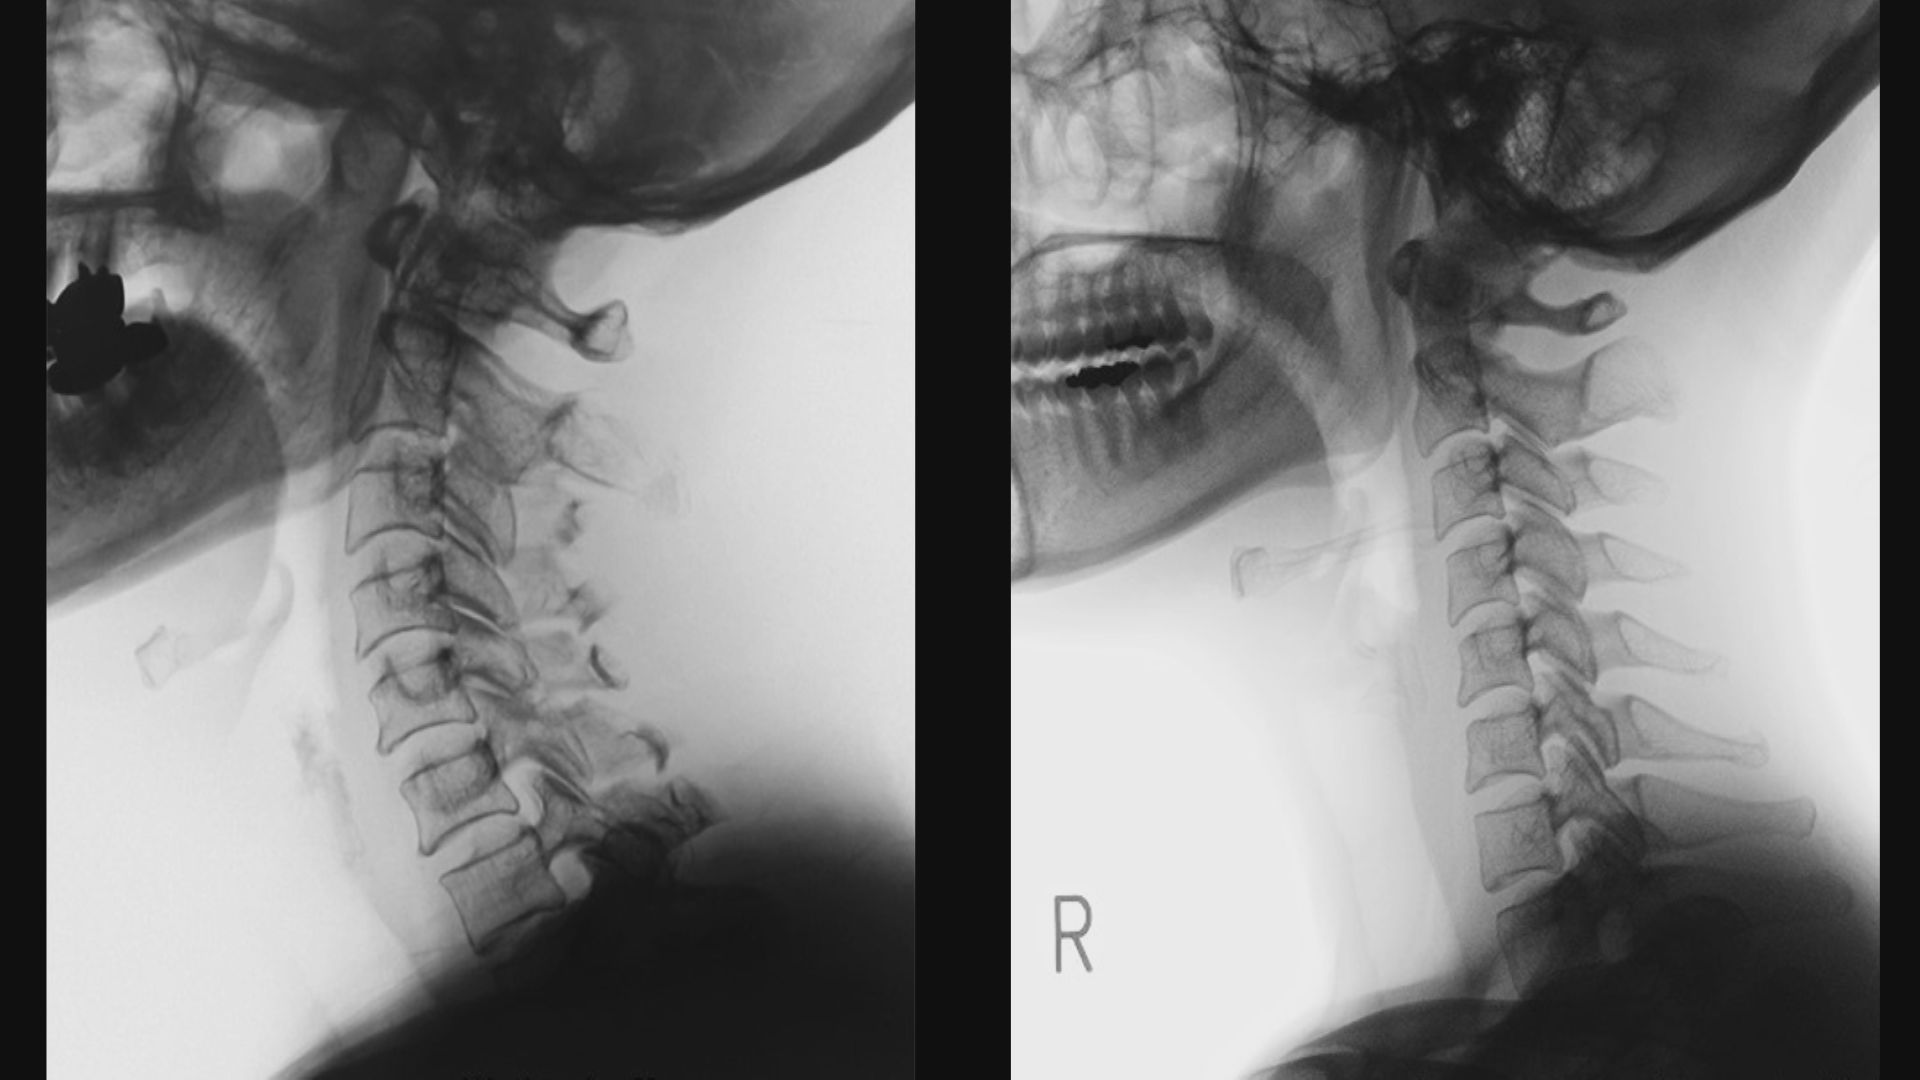

比較(右がストレートネック)

通常、頸椎は横から見るとS字に湾曲しています。

一方、ストレートネックは文字通り、真っすぐです。

レントゲン写真を並べると一目瞭然です。